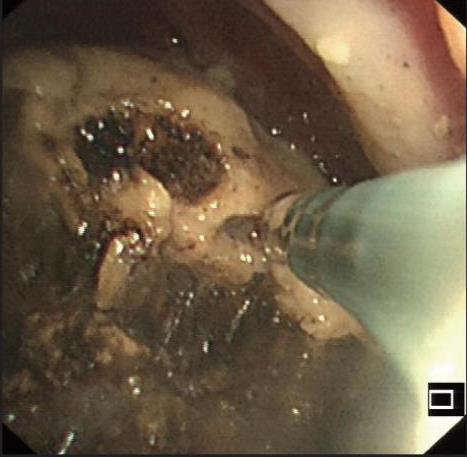

• 侵袭性肺真菌病的支气管镜表现及介入治疗效果

2025, 31(9):81-90. DOI: 10.12235/E20250317

摘要 (112) HTML (56) PDF 6.06 M (77) 评论 (0) 收藏

摘要:目的 探讨侵袭性肺真菌病(IPFD)的支气管镜表现,并评估介入治疗的安全性和疗效。方法 回顾性分析2018年5月12日-2025年5月12日于该院行支气管镜检查的35例IPFD患者的临床资料,观察IPFD的支气管镜表现及介入治疗效果。结果 共收集35例患者临床资料。其中,男22例,女13例,患者年龄(53±14)岁。基础疾病包括:血液系统恶性肿瘤10例,长期应用糖皮质激素者5例,2型糖尿病者4例,肺部恶性肿瘤2例,器官移植1例。胸部CT显示:肺部病变累及单肺叶者19例,累及多肺叶者16例。支气管镜下表现主要为:黏膜充血水肿29例(82.9%)、坏死物堵塞管腔22例(62.9%)、大量黏稠脓性分泌物17例(48.6%)、支气管部分狭窄或闭塞16例(45.7%)、黏膜坏死9例(25.7%)、黏膜出血5例(14.3%)、真菌球3例(8.6%)。其中,32例(91.4%)接受全身性抗真菌治疗,17例(48.6%)接受支气管镜局部两性霉素B灌注治疗,10例(28.6%)采用活检钳钳除病灶,6例(17.1%)采用冷冻探头冻取病灶,4例(11.4%)接受氩气刀治疗。28例(80.0%)临床症状明显改善,肺部影像学病灶缩小或消退;4例(11.4%)病灶稳定;3例(8.6%)未完成治疗。结论 IPFD多见于免疫抑制宿主,支气管镜常表现为:坏死物堵塞管腔、伴脓性分泌物、支气管管腔狭窄和局部黏膜充血水肿或坏死。全身抗真菌药物联合支气管镜下介入治疗,安全性高,且疗效好。